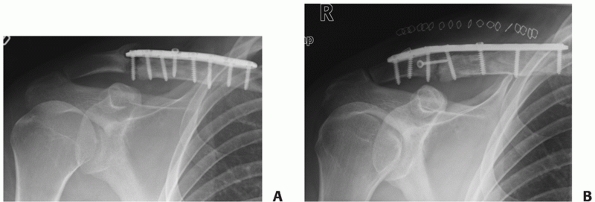

![]()  |

FIGURE 36-26 A.

Anteroposterior radiograph of a displaced distal clavicle fracture in a 38-year-old patient after falling off a mountain bike at high speed. Although the fracture was closed, there was significant bruising and swelling over the shoulder. The degree of displacement of this fracture suggests a high likelihood that delayed union or nonunion would result with nonoperative treatment. After the soft tissue swelling had subsided 10 days postinjury, operative fixation was performed with a plate specifically designed for the distal clavicle, allowing for the placement of four screws in the small distal fragment (B). The fracture healed uneventfully and the patient was able to return to work within a week of the surgery. C. Final follow-up radiograph following hardware removal for local soft tissue irritation, a common problem in this area, shows solid union.  |